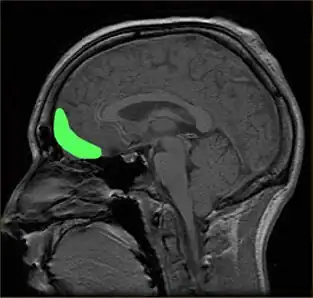

Orbitofrontal cortex, part of the prefrontal cortex that shapes decision-making

Although the precise neural mechanisms underlying disorders of impulse control are not fully known, the prefrontal cortex (PFC) is the brain region most ubiquitously implicated in impulsivity.[150] Damage to the prefrontal cortex has been associated with difficulties preparing to act, switching between response alternatives, and inhibiting inappropriate responses.[144] Recent research has uncovered additional regions of interest, as well as highlighted particular subregions of the PFC, that can be tied to performance in specific behavioral tasks.

The orbitofrontal cortex is now thought to play a role in disinhibiting,[152] and injury to other brain structures, such as to the right inferior frontal gyrus, a specific subregion of the PFC, has been associated with deficits in stop-signal inhibition.[153]